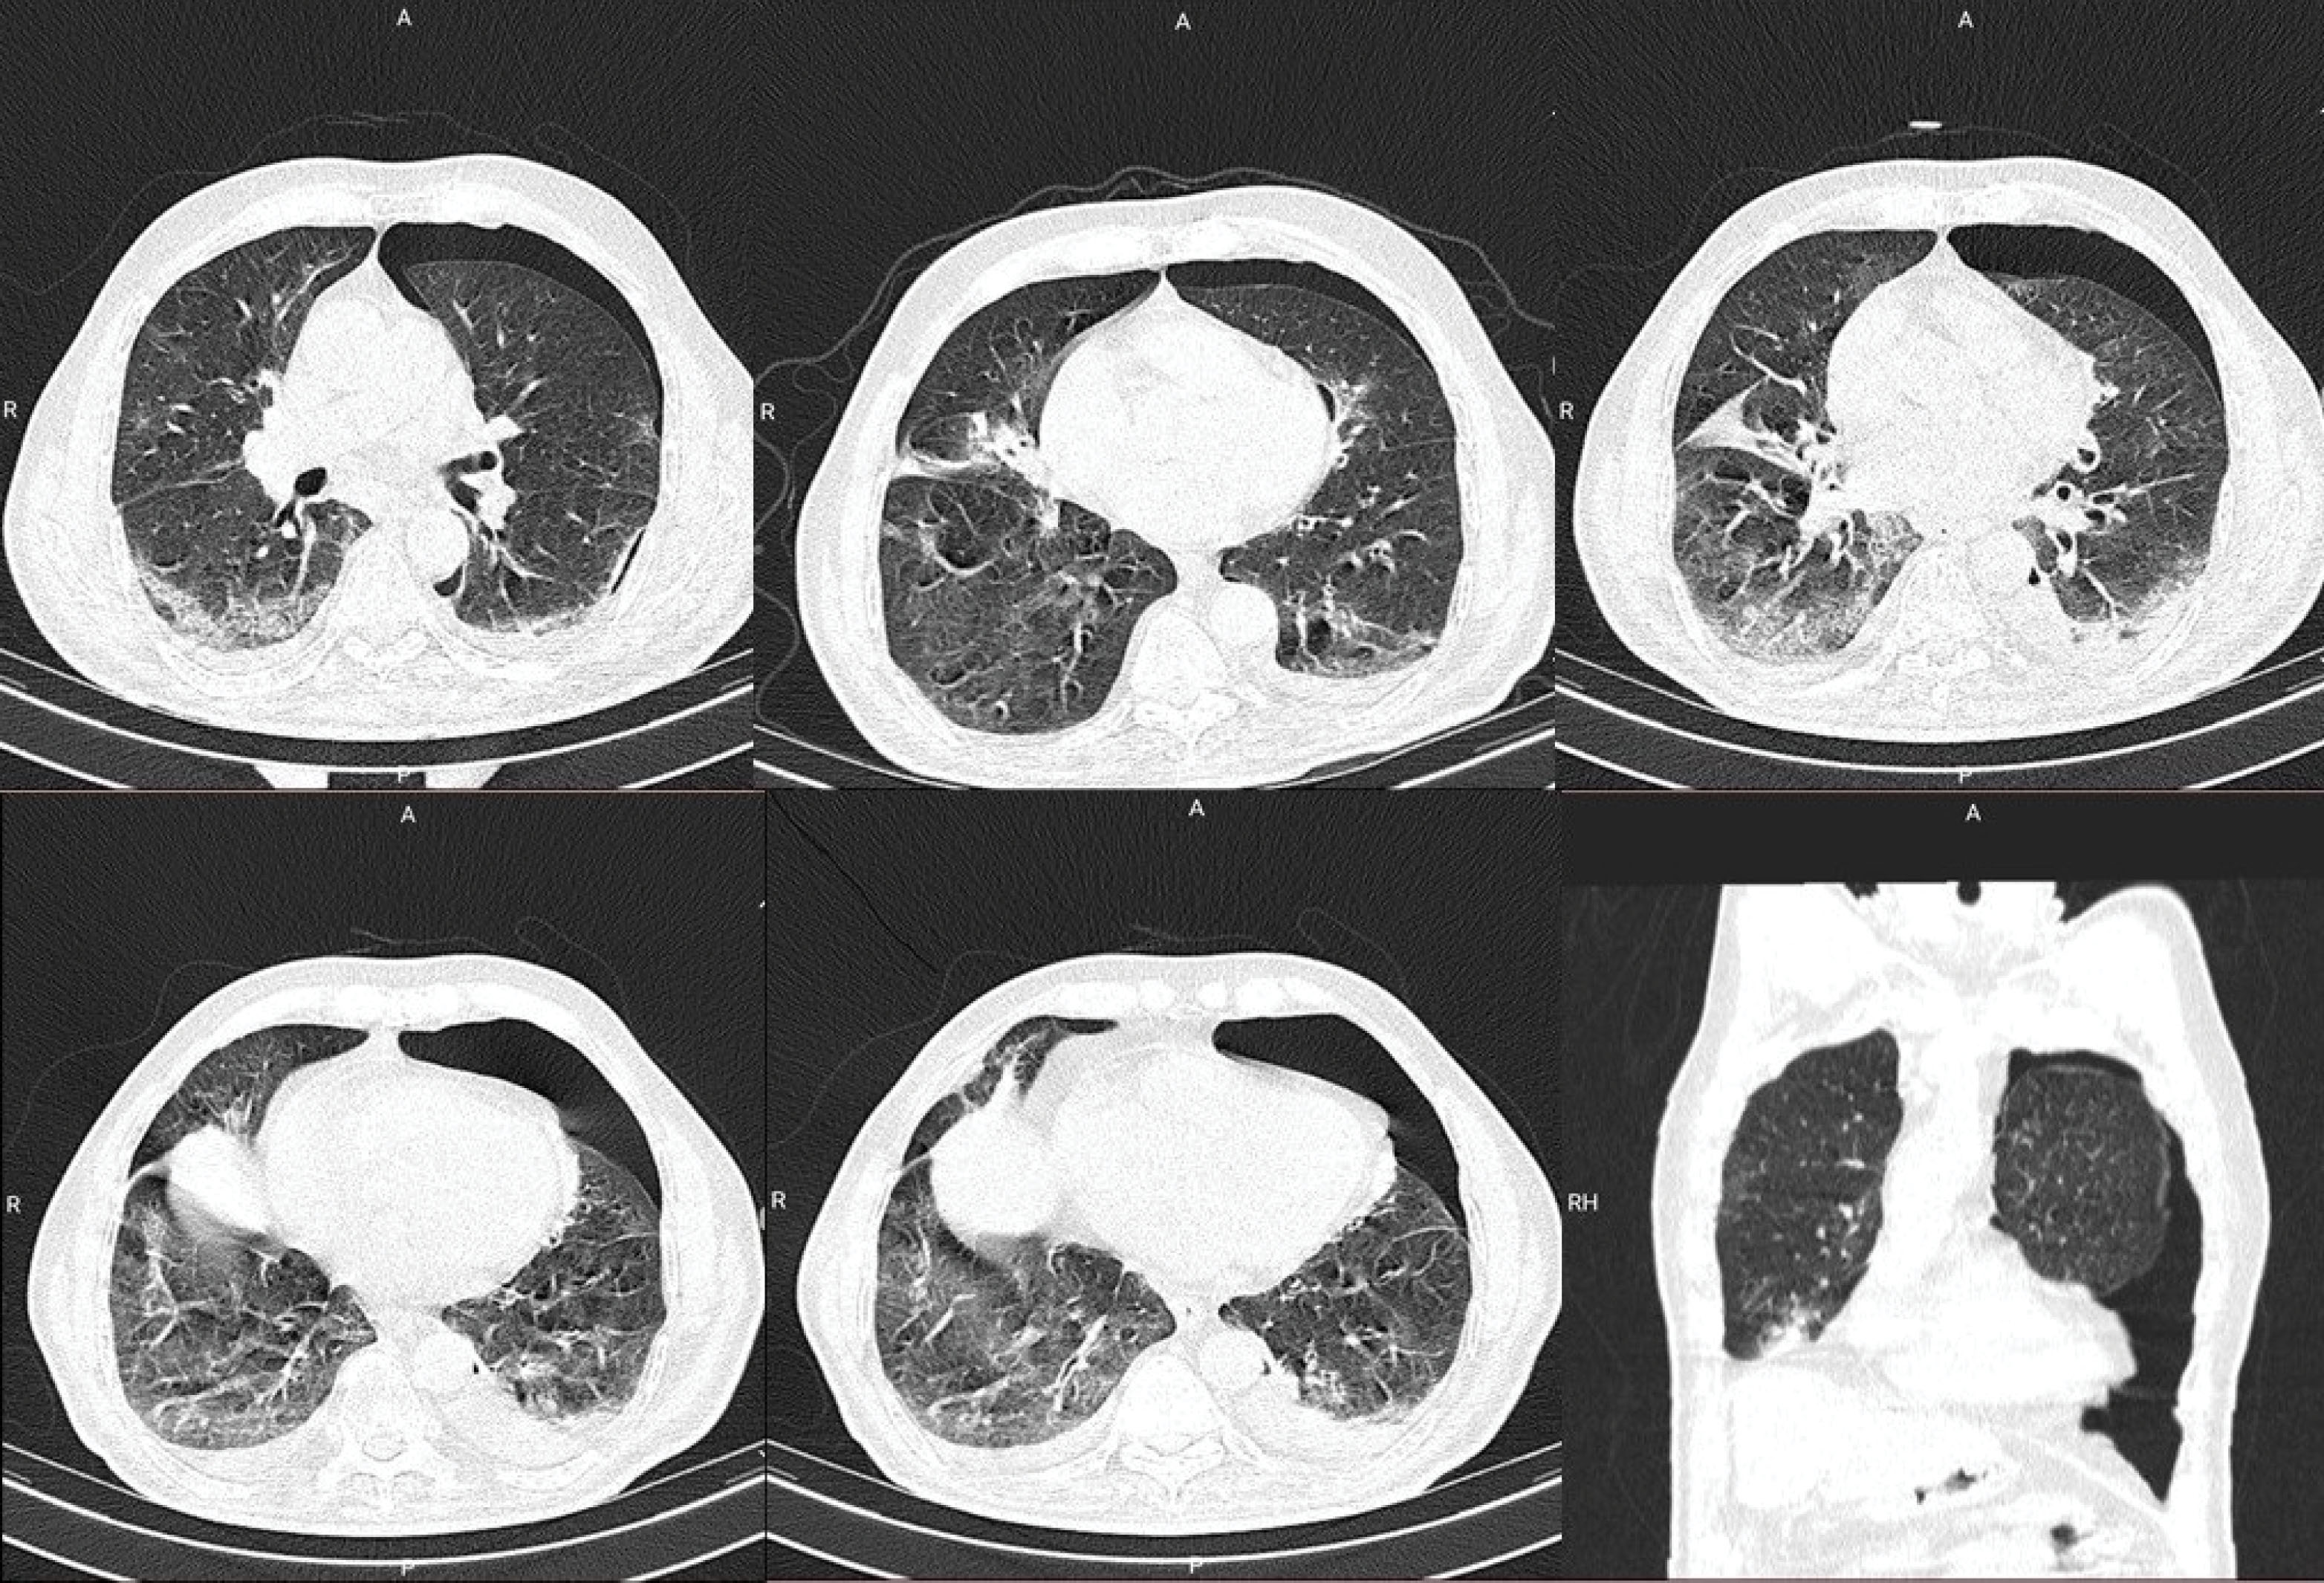

Figure 2.

Second CT of the patient taken after a rapid deterioration in clinical signs and symptoms. The pneumothorax had extended beyond its original boundaries and occupied over one-fifth of the thoracic cavity, which warranted insertion of a chest tube. Ground-glass-opacities also increased in size and frequency over the time between the two chest CTs

The patient had a chest X-ray performed which showed signs of pneumothorax, with a barely visible reduced lung marking in the periphery of the left lung. The patient had a second CT imaging done (), which showed a radiolucent peripheral space, a grossly visible visceral pleural edge and absent lung markings in the periphery. The diagnosis of an expanding pneumothorax was established, and utilizing the Colling’s method, the percentage of the pneumothorax was estimated to be 25.3%. The patient had an urgent consultation done with the pulmonology department, which recommended that a chest tube be inserted. The patient was stable after insertion of the chest tube, and had a complete absorption of the pneumothorax, and was discharged six days after the insertion of the chest tube.